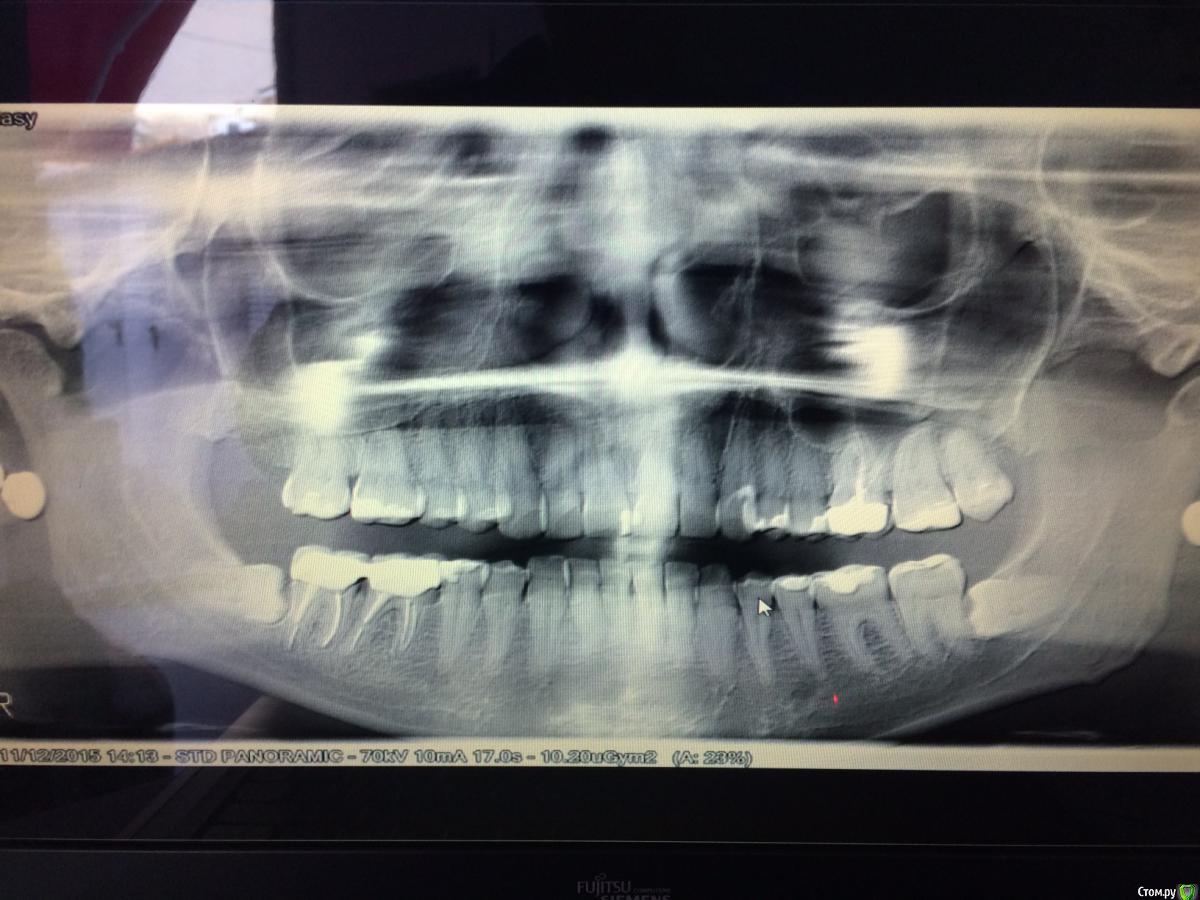

ЮлияЮ Опубликовано 14 декабря, 2015 Поделиться Опубликовано 14 декабря, 2015 Нужно удалять 8 левую, рядом два зуба под коронками, я боюсь что 8 им навредит и пища там плохо вычищается, большая вероятность кариеса. Врач сказал, что нерв проходит близко, боюсь удалять, боюсь последствий. Предлагают вставить в полость от 8 мембрану, чтобы соседний зуб не выпал. Что скажите? Какого врача посоветуете. снимок прилагаю Спасибо Ссылка на комментарий

AlexanderGudkov Опубликовано 14 декабря, 2015 Поделиться Опубликовано 14 декабря, 2015 (изменено) Нерв как нерв. Не так уж он и близко. Сделайте КТ для уточнения его положения и вперед) Изменено 14 декабря, 2015 пользователем AlexanderGudkov 2 Ссылка на комментарий

IvanK Опубликовано 15 декабря, 2015 Поделиться Опубликовано 15 декабря, 2015 Никаких проблем не вижу. Ищите Врача, для которого удаление таких зубов не проблема 1 Ссылка на комментарий